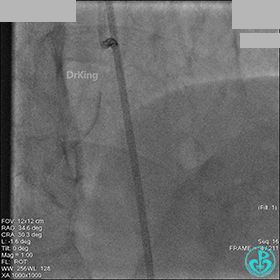

1周后再次上台,右冠脉3级血流,3段局限性严重狭窄,内膜模糊,应该是上次操作夹层遗留下的血肿。

先处理前降支开口严重狭窄并顺利植入前降支到左主干支架。